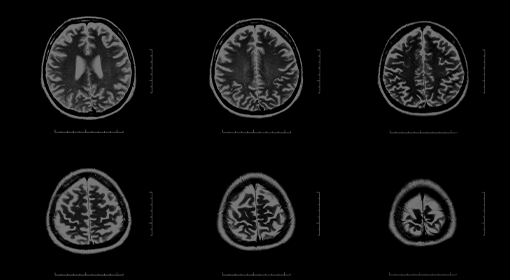

정밀 뇌영상 검사 및 종합적인 평가를 통해

영상 검사를 통환 뇌질환 조기 진단, 뇌혈관 질환 예방, 아산병원 출신 신경과 전문의와 세브란스 출신 재활의학 전문의 연계 협진